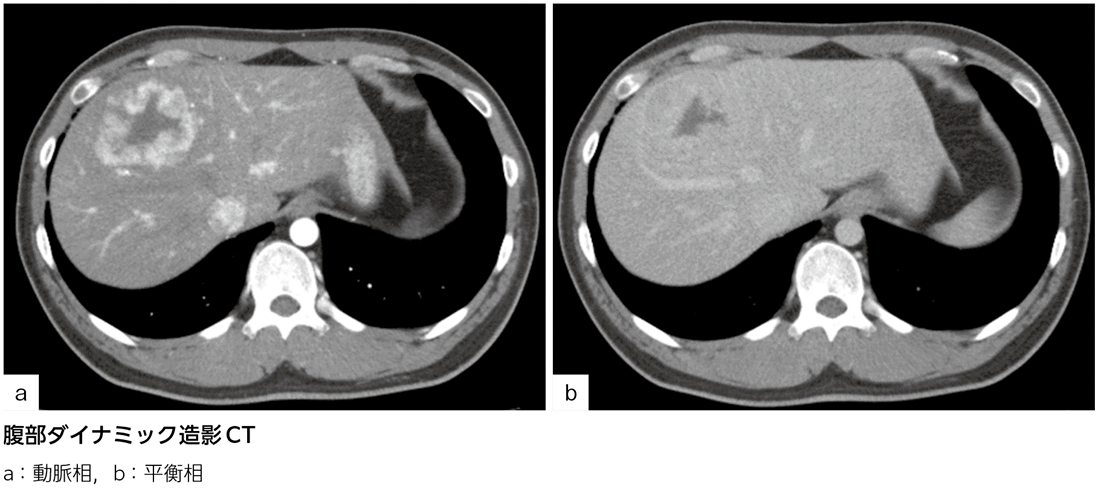

多血性腫瘍……診断は?[画像診断道場~実はこうだった(327)]

耐糖能障害を指摘され,血糖値コントロール目的で当院内科へ入院となった。入院中に施行した腹部ダイナミック造影CTで上記画像所見を認めた。